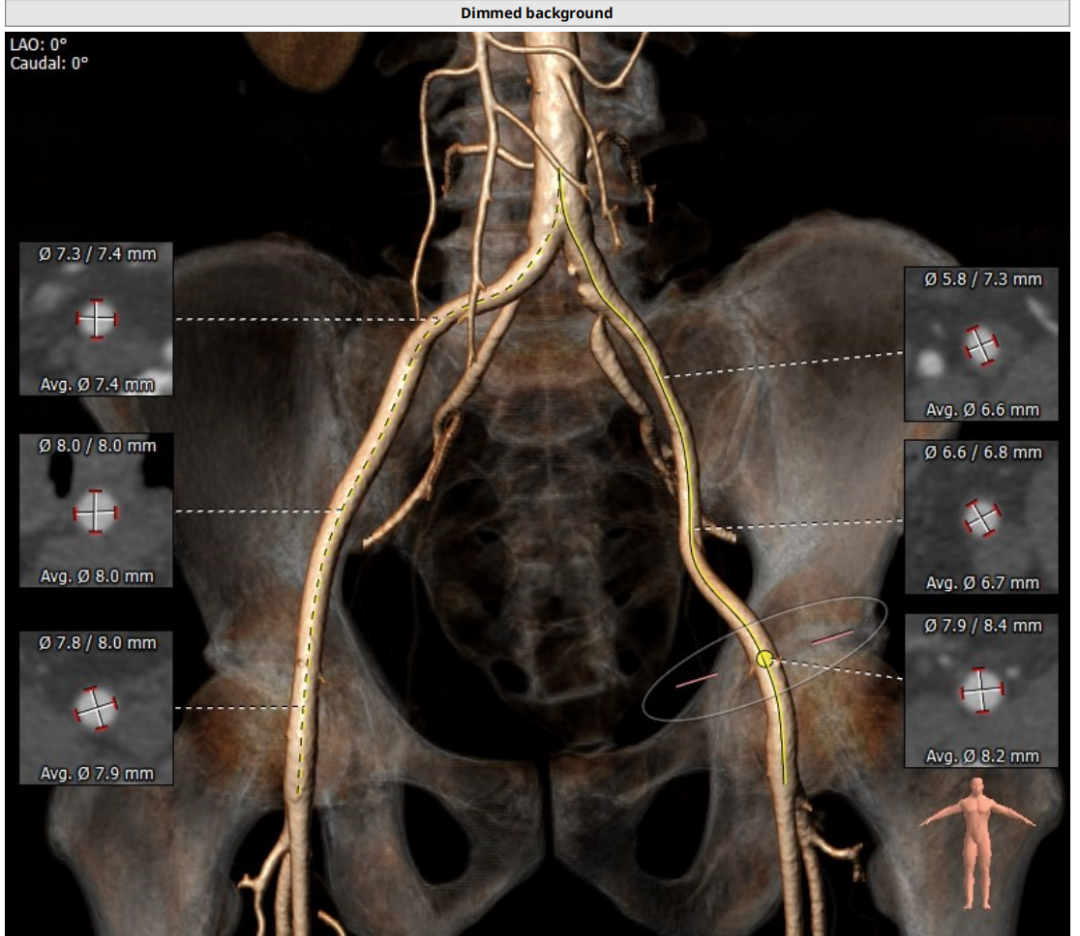

入路:入路观察是否有溃疡、钙化、迂曲、血管狭窄等情况,以判断夹层风险。该病人入路情况良好,优先选择右股作为输送系统主入路。

心尖薄,导丝塑性需注意形态,入路可,右股做为主入路。

入路直径足够,分叉点足够高。右股作为主入路。